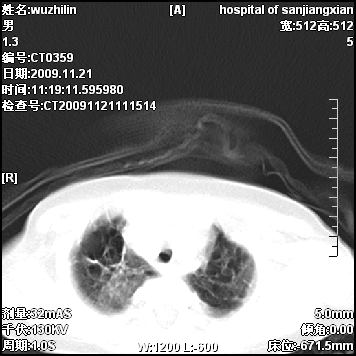

标题: PED3072: 1岁3个月患儿 胸部弥漫性病变 [打印本页]

标题: PED3072: 1岁3个月患儿 胸部弥漫性病变

弥漫性薄壁囊腔,胸膜下及肺底部占优势,双上肺磨玻璃密度影,首先考虑特发性肺间质纤维化,其次囊性肺纤维化,肺淋巴管平滑肌瘤病嗜酸性肉芽肿等;要结合临床综合考虑。

两肺布满多个薄壁含气囊腔,以下肺居多,伴磨玻璃样密度影,左侧气胸。两肺发育不全、两肺多发肺囊肿并感染,其次考虑肺囊腺瘤。